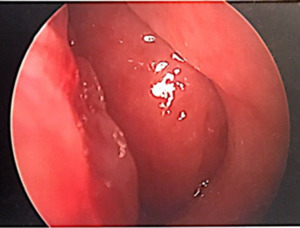

The patient’s physical exam was negative other than a hyponasal voice. Upon nasal endoscopy there were post surgical changes of the maxillary and ethmoid sinuses noted without purulent drainage as well as a large septal perforation. The entire nasopharynx was obstructed with a smooth, fleshy, rubbery mass inhibiting airflow through the nasal cavity (Figure 1).